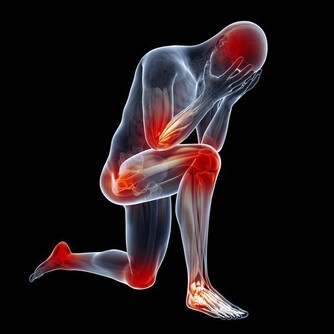

雖說在偏酸的環境下,鹼性磷酸鈣鹽容易溶解,導致骨骼內的有機成分相對較多,並因此使骨骼變得韌性有餘,硬度不足。

但實際上,鹼性磷酸鹽算是比較穩定的一類無機鹽,不是那種“輕佻的”、稍有“風吹草動”就會“改變立場”的物質。

常吃酸味食物,會影響骨骼發育,讓孩子長不高? 父母都該了解下

更重要的是,酸性食物被人體攝入後,並不是直接和骨骼接觸的,它要經過消化系統的消化吸收。

消化系統會根據體液的酸鹼情況,對營養物質進行“擇優錄取”——急需的、缺少的多吸收,反之則少吸收。

除此之外,人體的腎臟還是體內最重要的酸鹼平衡器官。

在腎功能正常的情況下,體內液體的酸鹼度將會維持在一個非常穩定的狀態(7.35~7.45)。體內酸多了,腎臟就會多排出酸,反之亦然。

這種非常穩定的酸鹼度,是不可能引起大量鹼性磷酸鈣鹽溶解這種“軒然大波”的。

可見,經常吃酸性食物,並不會引起骨骼內礦物質的溶解流失,更不存在影響長個子一說。